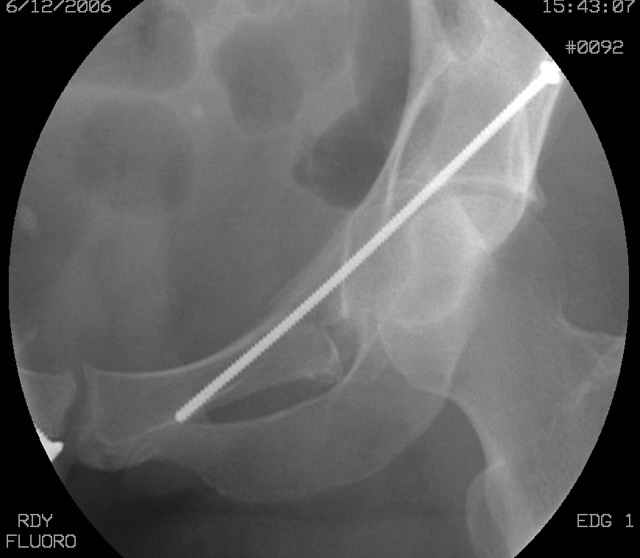

We seek the starting site (after reduction) with a thin wire guided by fluoroscopic imaging as the obturator-outlet combination image and also the inlet image...engage the wire tip into bone, incise around the wire, apply a soft tissue protection sleeve of known length over the wire, remove the wire, exchange thru the sleeve with an appropriate diameter drill (I use a 3.5mm most often), drill the glide pathway above and behind the joint to the fracture, exchange for a calibrated appropriate diameter drill, oscillate within the ramus to the pubis, measure depth using the calibrated drill and known sleeve length, do the math, remove the drill and insert screw, tighten, squirt the hole, close, stress the fixation, supplement if needed.